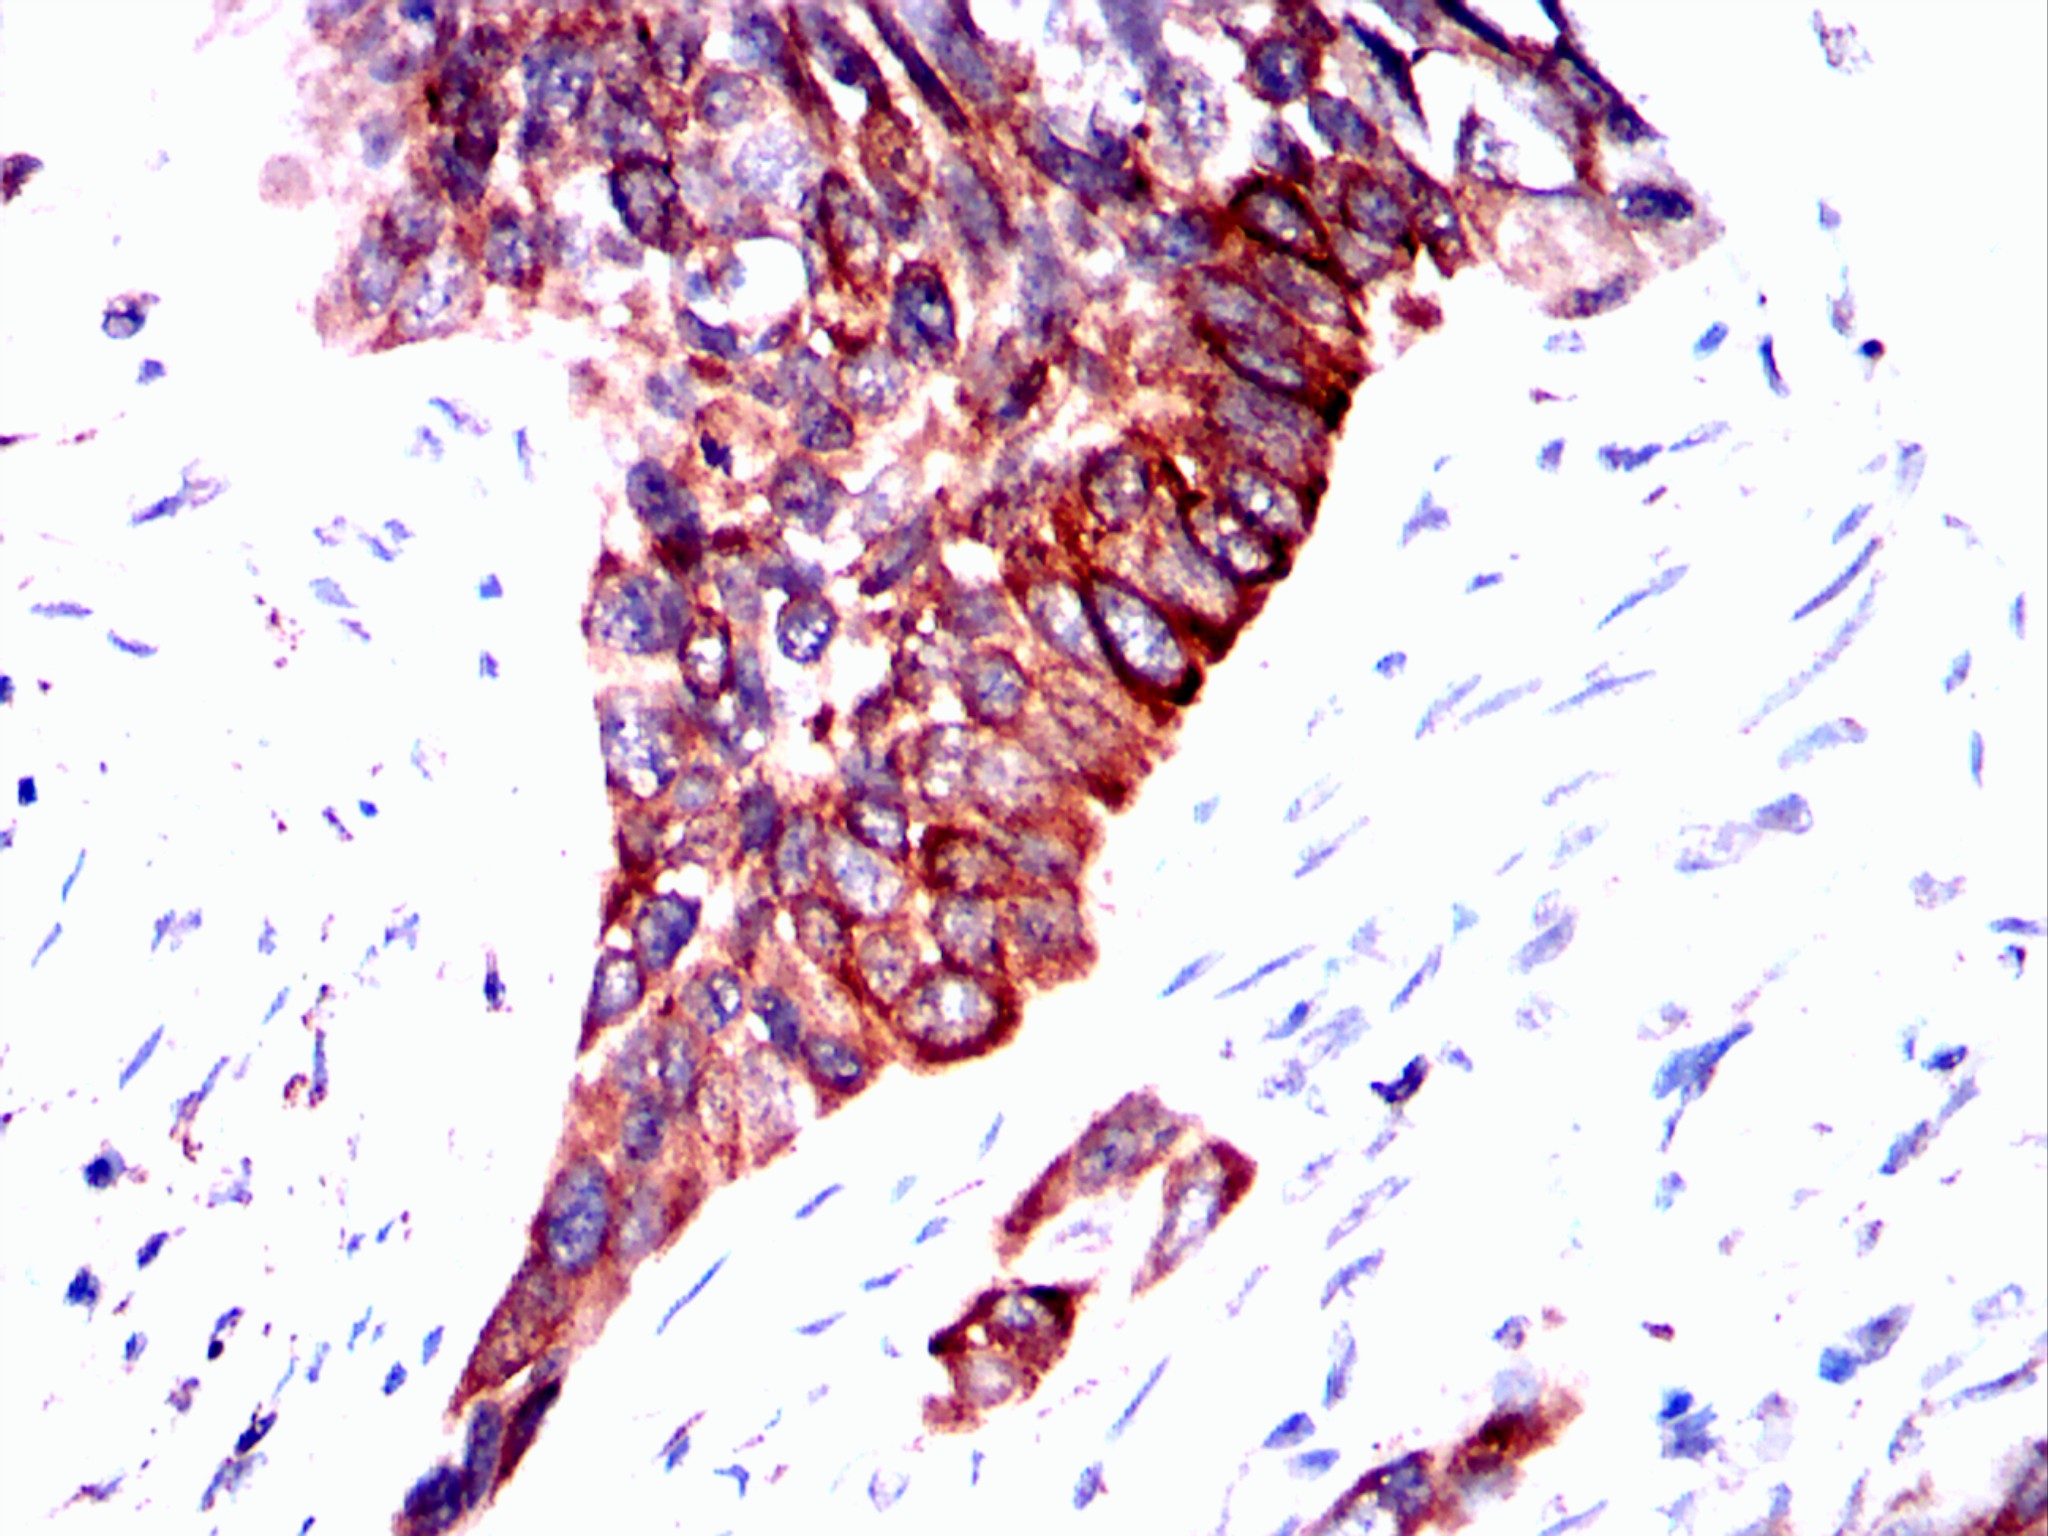

Immunohistochemical analysis of paraffin-embedded lung cancer tissues using ERBB3 mouse mAb with DAB staining.